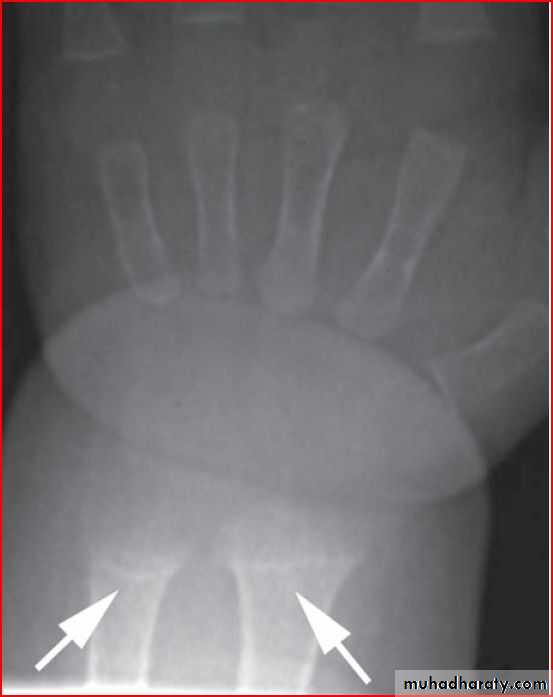

X ray of wrist showing cupping fraying splaying

Dx >>> rickettwo labrotary investigation 1. alkaline phosphatase elevation

2. s.calicium low or normal

ricket